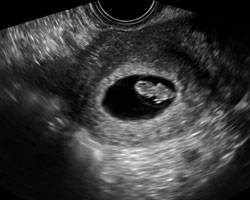

Ecografia de 7 semanas

Na 7ª semana de gravidez, durante a primeira ecografia, já se poderá ver o embrião em forma de ponto branco e, no seu interior, o coração a bater. Os aparelhos de ultrassons mais modernos também permitem ver o coração a cores e ouvir os seus batimentos.

O ideal é realizar esta ecografia por via vaginal, pois por via abdominal é ainda cedo para ver o embrião.